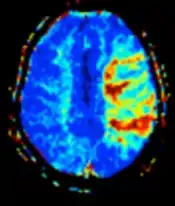

| Diffusion weighted (DWI) | Conventional | DWI | Measure of Brownian motion of water molecules.[78] | High signal within minutes of cerebral infarction (pictured).[79] |  |

| Apparent diffusion coefficient | ADC | Reduced T2 weighting by taking multiple conventional DWI images with different DWI weighting, and the change corresponds to diffusion.[80] | Low signal minutes after cerebral infarction (pictured).[81] |  | |